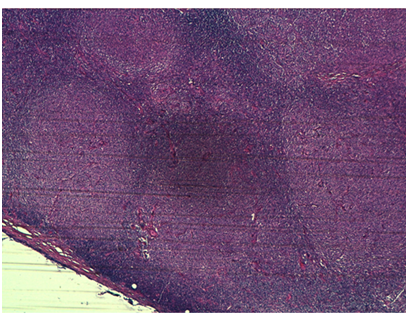

Figure 4 Follicular pattern in inguinal adenopathy. Tumor composed of atypical large lymphoid cells with pleomorphic nuclei and prominent nucleolus

Figure 5 Follicular pattern in colon sample.